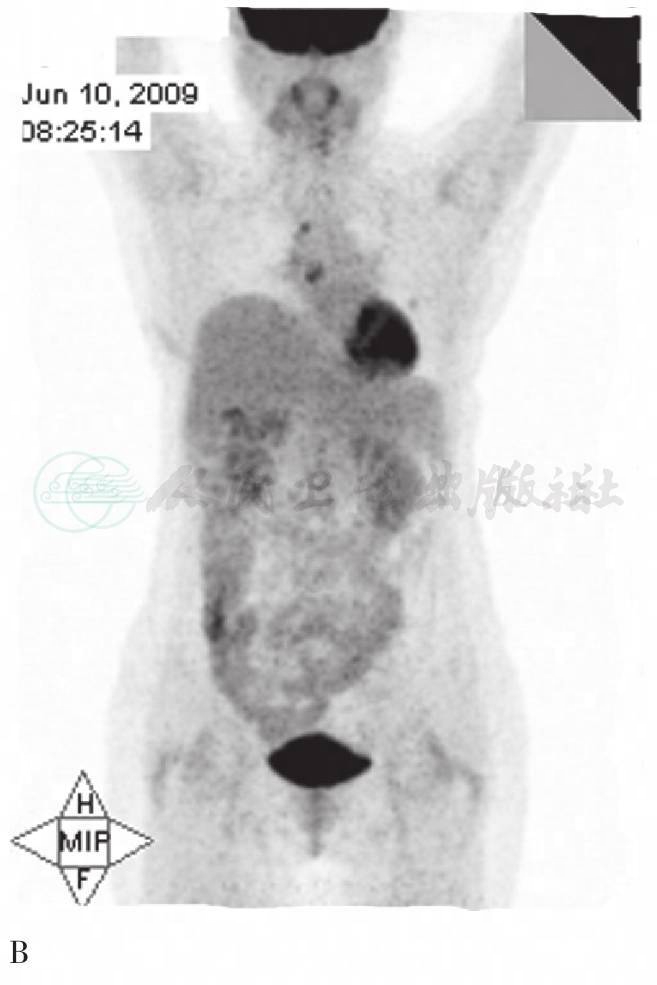

图1 PET MIP显像

A. 第一次PET图像:右侧气管旁和隆突下多发淋巴结肿大,放射性摄取不均匀增高、浓聚,部分为环形浓聚。右侧肋膈角区可见局灶性放射性浓聚;B. 4个月后复查图像:隆突下淋巴结肿大,放射性增高;右侧气管旁可见小灶状放射性增高